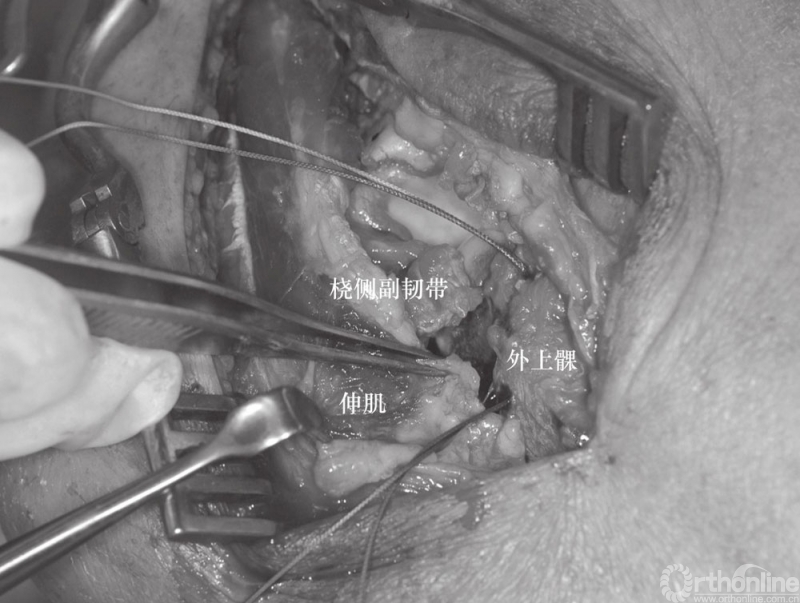

(2) 患者采用全麻、侧卧位,入路采用外侧入路,该入路便于切开复位、暴露肘关节、桡骨头重建和置换、固定冠状突以及后外侧韧带复合体的修复。外侧皮肤切口以肱骨外上髁为中心。前臂保持旋前位以增大骨间后神经与手术区域的距离。与单纯的桡骨头骨折采用的经肘肌和尺侧腕伸肌间的Kocher's间隔入路不同,对“恐怖三联征”患者可以利用损伤本身所造成的间隙进行暴露,而不需要特意的切开关节囊。损伤本身会导致关节囊、桡侧副韧带及大部分外侧肌肉软组织的破坏(图3)。

图7 采用外科缝线通过外上髁骨隧道进行缝合,修复撕裂的桡侧副韧带

该韧带复合体在维持肘关节内翻时的稳定具有重要作用,尤其是当尺侧副韧带也存在损伤需要修复时。采用带线锚钉将组织缝合修复并固定至肱骨外上髁(图8)。

如果伸肌总腱止点损伤应进行修复,Kocher's间隙的筋膜也应修补(图9和图10)。如果在修复桡骨头及外侧副韧带后,肘关节屈曲40°以上仍发生半脱位,则还需经内侧入路,以同样方法修复内侧韧带复合体(图11)。